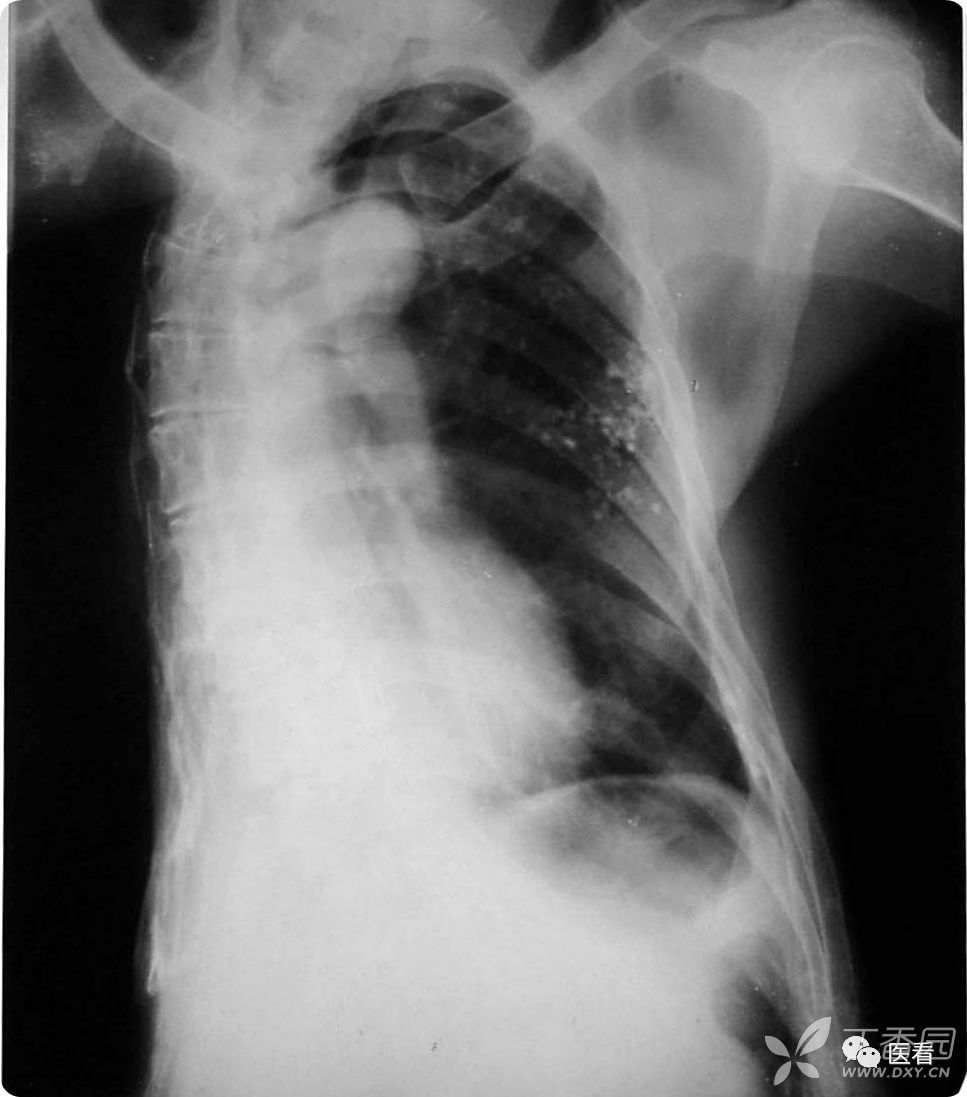

陈旧性肺结核导致的胸廓塌陷?脊柱弯曲?

男,55岁,右肺结核复查。陈旧性肺结核并脊柱畸形?

其实这是建国初期,为了治疗肺结核患者做了右侧 胸部切除术!右侧胸廓、右肺全部缺失。